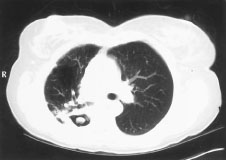

Sinal do "crescente aéreo" em aspergilose pulmonar avançada

Do acervo do Dr. P. Chandrasekar; usado com permissão

Veja esta imagem em contexto nas seguintes seções: